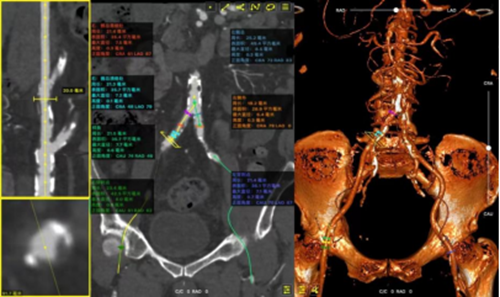

在等待择期TAVR手术的过程中,因新冠防控措施全面放开,罗大爷不幸感染新冠病毒。在回家调养休息半个月后,“阳康”的罗大爷于1月8日再次返院。洪浪及李林锋积极组织我院TAVR团队(包括心内科、心外科、麻醉科、超声科、CCU)进行相关术前讨论。总结病例特点如下:1.Type1型(横裂式)二叶瓣,重度钙化,钙化延伸窦底,瓣口面积0.48;2.患者室间隔增厚,心室较小,左右冠瓣叶较长,窦宽相对瓣膜可,右冠存在风险,瓣膜释放可回收极限处评估冠脉,弓部角度可;3.手术入路:双侧股动脉不迂曲,分叉低,左右髂总钙化斑块、溃疡,股动脉内径稍小;4.瓣膜球囊选型:建议20mm球囊,首选TAV27,备24。

在充分评估病情后,李林锋考虑到,如果实施全麻、气管插管、经食管超声等多种操作,患者的麻醉时间及手术时间延长,容易引发术中循环不稳定,且术后感染机会增加。经与麻醉师沟通后,决定在诱导麻醉状态下,不行气管插管及经食管超声心动图,经胸超声指导下行“一站式”冠状动脉支架植入(PCI)+经导管主动脉瓣置换术(TAVR)。